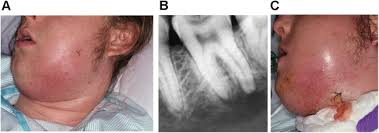

심한 치근단 농양으로 응급상황이 온 경우

많은 환자들이 증상이 없기 때문에 치료를 거부합니다.

"증상이 없는데 왜 치료를 권유 하느냐??" 라는 소리를 가장 많이 듣습니다.

저희 치과의사들이 가장 곤욕스러운 경우이죠.

하지만 과잉진료 말을 듣더라도, 말을 해드리지 않을 수는 없습니다.

전문가 입장에서 해당 질환의 말로를 잘 알고 있기 때문입니다.

상기 사진 처럼 증상이 발현된 경우 응급 상황이 올 수 있고

심한 경우에는 사망까지 끌고가는 무서운 질환 입니다.